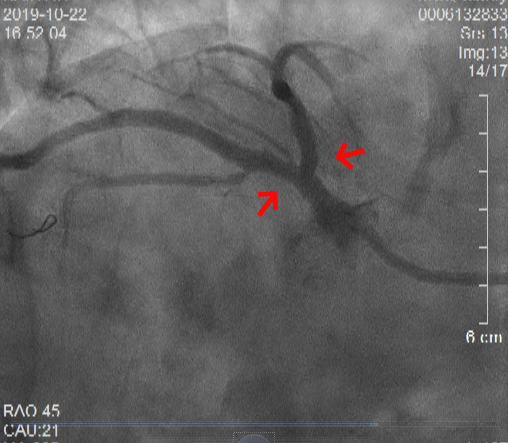

術前冠狀動脈造影顯示:鏡像右位心、前降支和回旋支開口處嚴重病變

入院第二天,心內科柴大軍主任醫師為核心的介入團隊為俞老先生進行了評估。此時俞老先生已可平臥,柴大軍主任醫師當機立斷為其行經皮冠狀動脈介入治療(PCI)。冠狀動脈造影顯示,俞老先生是極其罕見的右位心合并疑難的左主干分叉病變。